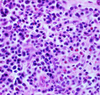

Pathogenesis (img)

Grain overload, rumenal acidosis, mucosal damage, opportunistic fungal infection, vasculitis, ischemia and mucosal ulceration